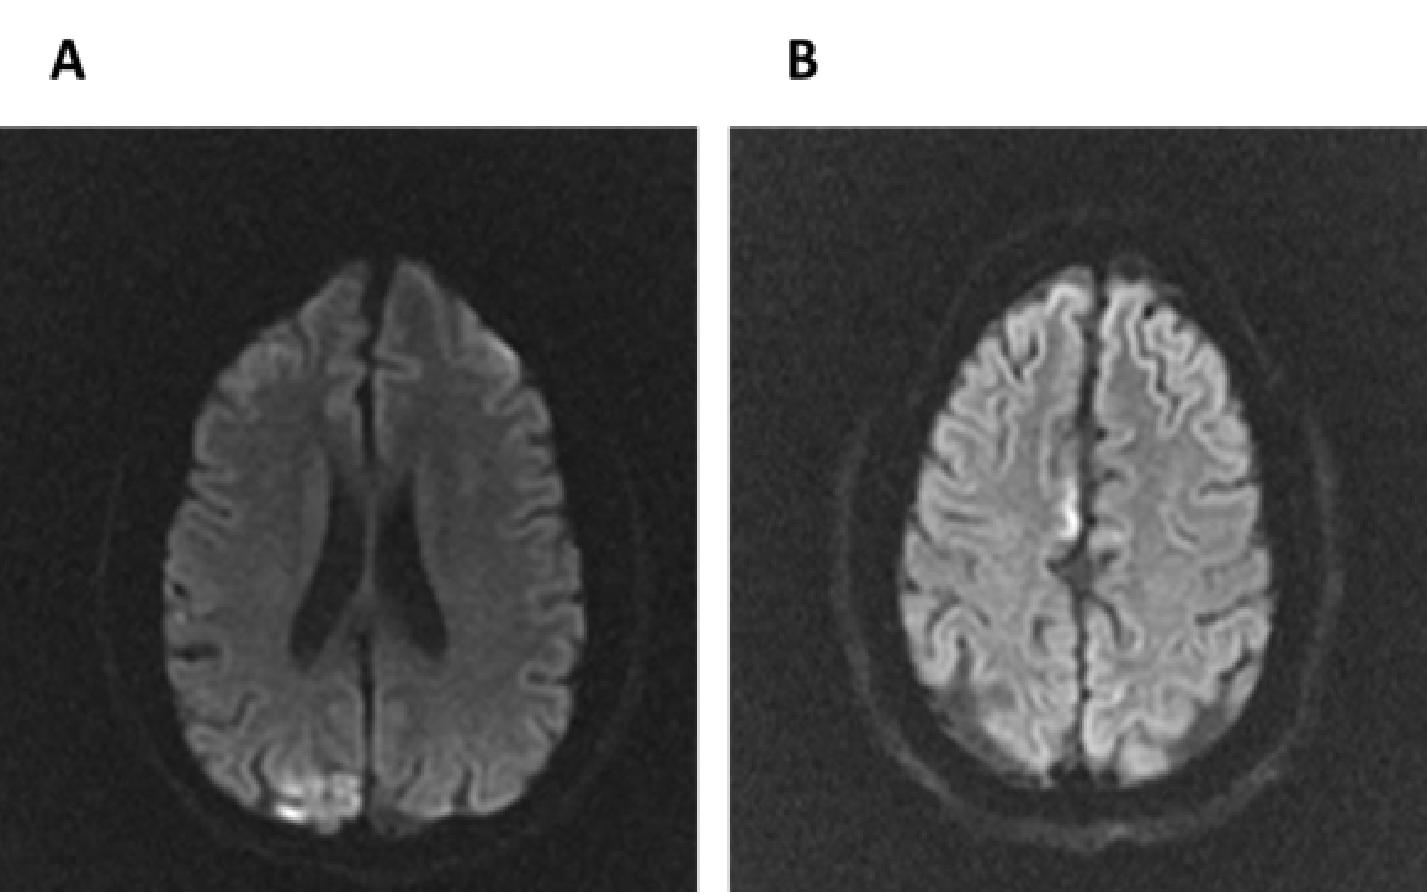

It is the most distinctive, although non-pathognomonic, disorder of MELAS syndrome, with an estimated prevalence between 31% and 90% of patients [7]. Its presentation is usually subacute, and the more commonly related symptoms are epileptic seizures, visual symptoms (especially cortical blindness) or a sensory-motor focal deficit. Brain MRI images show lesions that simulate an ischemic stroke, but do not have a distribution that corresponds to a defined vascular territory (Figure 1). The lesions predominate in the parietoccipital regions, can occur simultaneously in both hemispheres, are preferentially distributed in the cerebral cortex, and in some patients have an intermittent temporal pattern, disappearing withpout leaving sequelae [8].

In the acute phase, brain CT shows hypodense cortical lesions, while MRI T2 and FLAIR weighted images show hyperintensities, and T1 weighted images show cortical edema, and post-contrast linear enhancement. In subacute phases, lesions may show gyri cerebral cortex hyperintensities in T1 weighted images and hypointensities in T2-FLAIR. The presence of hypointense cystic-like lesions inside the cerebral cortex suggests the diagnosis of MELAS syndrome ("black nail sign") [9]. In chronic phases of the disease, the lesions can leave sequelae as encephalomalacia, gliosis and cortical atrophy.